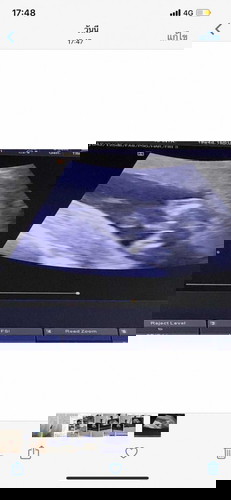

ท้องแรก 18 w4D

แม่ๆจ๋า น้องเป็นผู้ชาย หรือ ผู้หญิงค่ะ

ชายจ้า ชัดขนาดนี้หมอไม่บอกหรอค่ะ